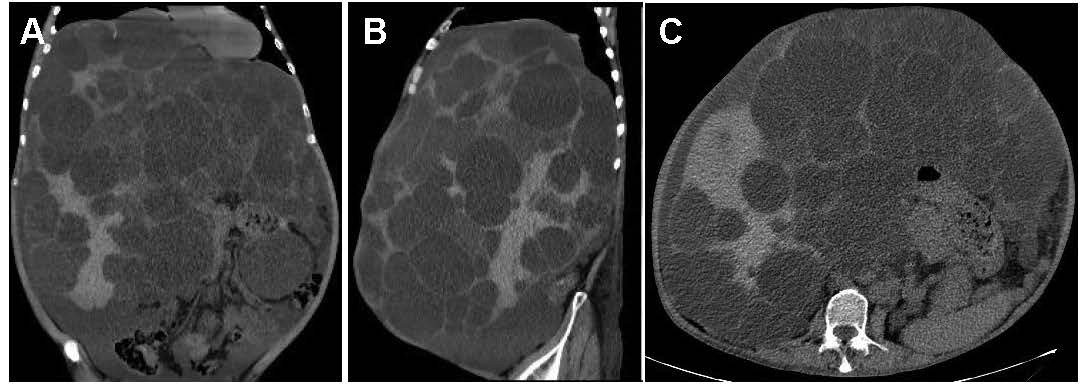

A 61-year-old man presented for routine health checkup. The patient was asymptomatic. His medical history was autosomal dominant polycystic kidney disease (ADPKD). Laboratory results and urinalysis were unremarkable. Abdominal computed tomography showed innumerable hepatic cysts of different sizes and diffuse small renal cysts (Figures 1A-1C). Polycystic liver disease (PCLD) is divided into the isolated form and PCLD associated with ADPKD, relevant to genetic defects including PKD1 and PKD2 mutations, which belongs to a family of hepatic ductal plate malformations with variable presence of other components of biliary dysgenesis [1]. PCLD is the most prevalent extrarenal manifestation, which frequently do not compromise liver function but may produce massive hepatomegaly and abdominal discomfort [2]. The liver cysts are not present at birth but develop over time as fluid accumulates, which is commonly modulated by genetic factors, age, pregnancy, and female gender [3]. When complications occur, such as intracystic hemorrhage, infection, cystadenocarcinoma, biliary obstruction, Budd-Chiari syndrome and post-traumatic rupture, surgical intervention is required. Surgical procedure commonly includes cyst aspiration and sclerosis, transcatheter arterial embolization, and fenestration and hepatic resection. In this patient, cyst complications were not identified and he continues routine outpatient follow-up.

Figure 1. A-C. Abdominal computed tomography reviews.